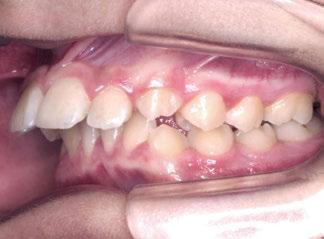

La exploración intraoral (figuras 4 a 8) revela una Clase II molar y canina completa, líneas 1/2 dentarias superior 0,5 mm e inferior 1 mm ambas desviadas hacia la derecha, los incisivos superiores excesivamente protruidos y vestibulizados (seguramente debido a la interposición del labio inferior), resalte de 13 mm y sobremordida 2/3 de corona. La discrepancia oseodentaria

inferior es de -3,5 mm y la curva de Spee de 4 mm.

Castañeda-Zetina y cols. realizaron un estudio para comparar las maloclusiones en niños asmáticos y sanos, en el cual se incluyeron 186 pacientes de entre 5 y 12 años. Los resultados obtenidos fueron que más del 50% de los niños asmáticos tienen respiración oral. Las principales alteraciones oclusales presentadas eran mordida abierta anterior y mordida cruzada posterior, menos frecuente; además de una menor frecuencia de clase III, solo un 11,6%, ya que el cambio postural de estos pacientes favorece la entrada del aire inclinando la cabeza hacia atrás y favoreciendo la aparición de clase II al posterorrotar la mandíbula. Estas modificaciones posturales van a producir alteraciones maxilares y desequilibrio en los m ú sculos periorales; por ello, su detección precoz ayudará a resolver el problema con un abordaje multidisciplinario y dando armonía al complejo dentoesquelético (56).